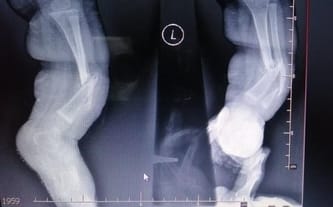

W czasie ciąży nic nie wskazywało na to, co wydarzy się tuż po przyjściu na świat. Lekarze nie mieli wątpliwości podczas badań, że noszę w brzuchu zdrowe dziecko. Tym większy był szok, który spotkał mnie po powrocie do domu z noworodkiem. Kilka dni w szpitalu po porodzie minęło w okamgnieniu, a później brutalne zderzenie z rzeczywistością. Pierwsza kąpiel, przebieranie, pamiętam doskonale te emocje. Ekscytację związaną z pojawieniem się nowego członka rodziny. Kiedy rozebrałam Natana w mojej głowie zapaliła się lampka alarmowa. Widziałam z jego nóżką co jest nie tak. Byłam przerażona. Już na pierwszy rzut oka było widać, że układ kości nie jest prawidłowy. Nóżka jest zdeformowana, kość piszczelowa wygięta w łuk, a stópka jest wykrzywiona. To był pierwszy szok. Kolejny był znacznie większy, kiedy dotarło do mnie, że lekarze w naszym szpitalu niczego nie zauważyli. Nikt, nawet słowem nie wspomniał o tym, że mój synek boryka się z chorobą!

Kiedy Natan miał 3 tygodnie, kiedy zaatakował go wirus. Trafiliśmy do szpitala. Mój stres był ogromny. Nie mogłam znaleźć sobie miejsca, bałam się o jego życie. Dla takiego maluszka każda infekcja to walka na śmierć i życie. Kiedy Natanek wygrał walkę o zdrowie i pokonał wirus, lekarze zaczęli konsultować sprawę chorej nóżki. To dzięki nim wiedziałam co robić dalej, dostałam skierowania do kolejnych specjalistów. Poszukiwania diagnozy rozpoczęły się na dobre. I chociaż Natanek ma niecały roczek odwiedził gabinet lekarski znacznie więcej razy niż niejeden dorosły. Teraz już wiem, że noga jest bardzo słaba, a kość może łamać się w każdej chwili. Nawet najmniejsze uderzenie, przemieszczenie może prowadzić do złamania.

Informacje lekarzy bardzo nam pomogły, ale wraz z nimi dostaliśmy wiadomość, która zwaliła nas z nóg. Operacja prowadząca do zdrowia i sprawności synka mogłaby się odbyć dopiero za 10-15 lat. To czas, którego nie mamy! Te wszystkie lata stracone na czekaniu… Wiem, że istnieją dzieci, które uczą się chodzić z tą chorobą, wiem, że deformacja nie przekreśla rozwoju, ale powoduje potworne komplikacje. Chora noga przez złamaną kość nie rośnie tak samo szybko jak zdrowa. Od jakiegoś czasu dostrzegam dysproporcję w ich długości. Niestety, wiem, że jeśli to zaczęło się tak szybko, będzie tylko gorzej! My nie możemy czekać, nie mamy czasu do stracenia! Zbyt krótka noga prowadzi do poważnych wad kręgosłupa. To zagrożenie, z którym będzie borykać się przez całe życie.